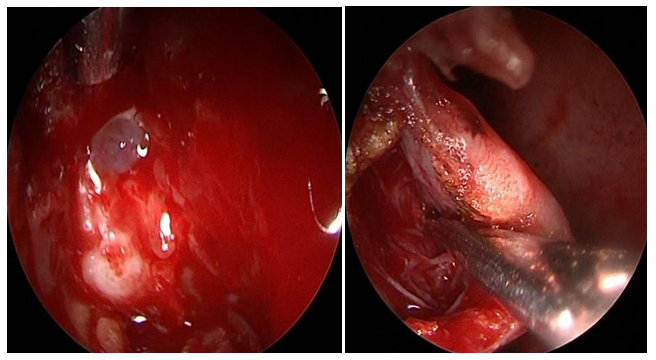

Intranasal MC was the most frequent lesion (6/5) and there was one patient with MEC (1/6). Five cases were idiopathic and one patient had history of transnasal surgery for a tumor of the sellar region and sphenoid plane 15 days before. 83,3% of the cases were primary surgeries and one patient had 3 prior MC surgeries. In 2 cases the MC was located in the sphenoid lateral wall (Figures 1A-B), one was located in the sphenoid roof (Figure 2), 2 in the cribriform plate and one patient, with MEC diagnosis, had it located in the frontal sinus. 66,6% had anterior rhinorrhoea (4/6) (Table 1). All patients were studied before surgery, only in four of them (66,6%) the lesion location was detected by at least one of the studies (CT, MRI and/or endoscopy). For one patient with MC of the lateral sphenoid wall intrathecal fluorescein was used prior to surgery (10cc of CSF were extracted by lumbar puncture and mixed with 0.2ml of 5% fluorescein, then 1ml per minute was delivered by intrathecal injection. We performed a multilayer closure technique in all patients (Figures 3A-C). In 4 cases we used autologous fat with mucoperichondrium (Figures 4A-B) and (Figures 5A-C) and in 2 cases autologous cartilage with mucoperichondrium. We used an intranasal transpterygoid approach for one case of lateral sphenoid wall mucocele, a Draf III technique in une case of frontal sinus MEC (Figures 6A-E). During the immediate postoperative period, one patient had acute meningitis that resolved with intravenous empirical antibiotics. One patient had a CSF leak recurrence 4 months after surgery. He was treated by external approach and had no relapse. No complications during postoperative follow up. The success rate of the reconstructions performed by endonasal approach was 83.33% (5/6). The average follow-up of the patients was 15 months.

Figure 4A Cribiform plate MC. B: Multilayer closure using autologous fat and mucoperiosteal lateral nasal wall flap.

Figure 5A Cribiform plate MC. B-C: Multilayer closure using autologous fat and mucoperiosteal middle turbinate flap.